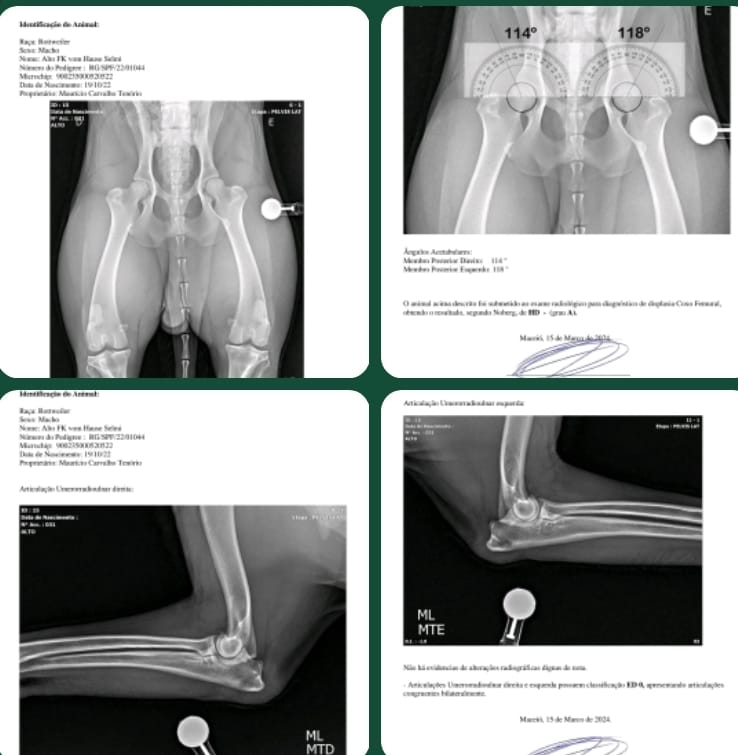

Raio X